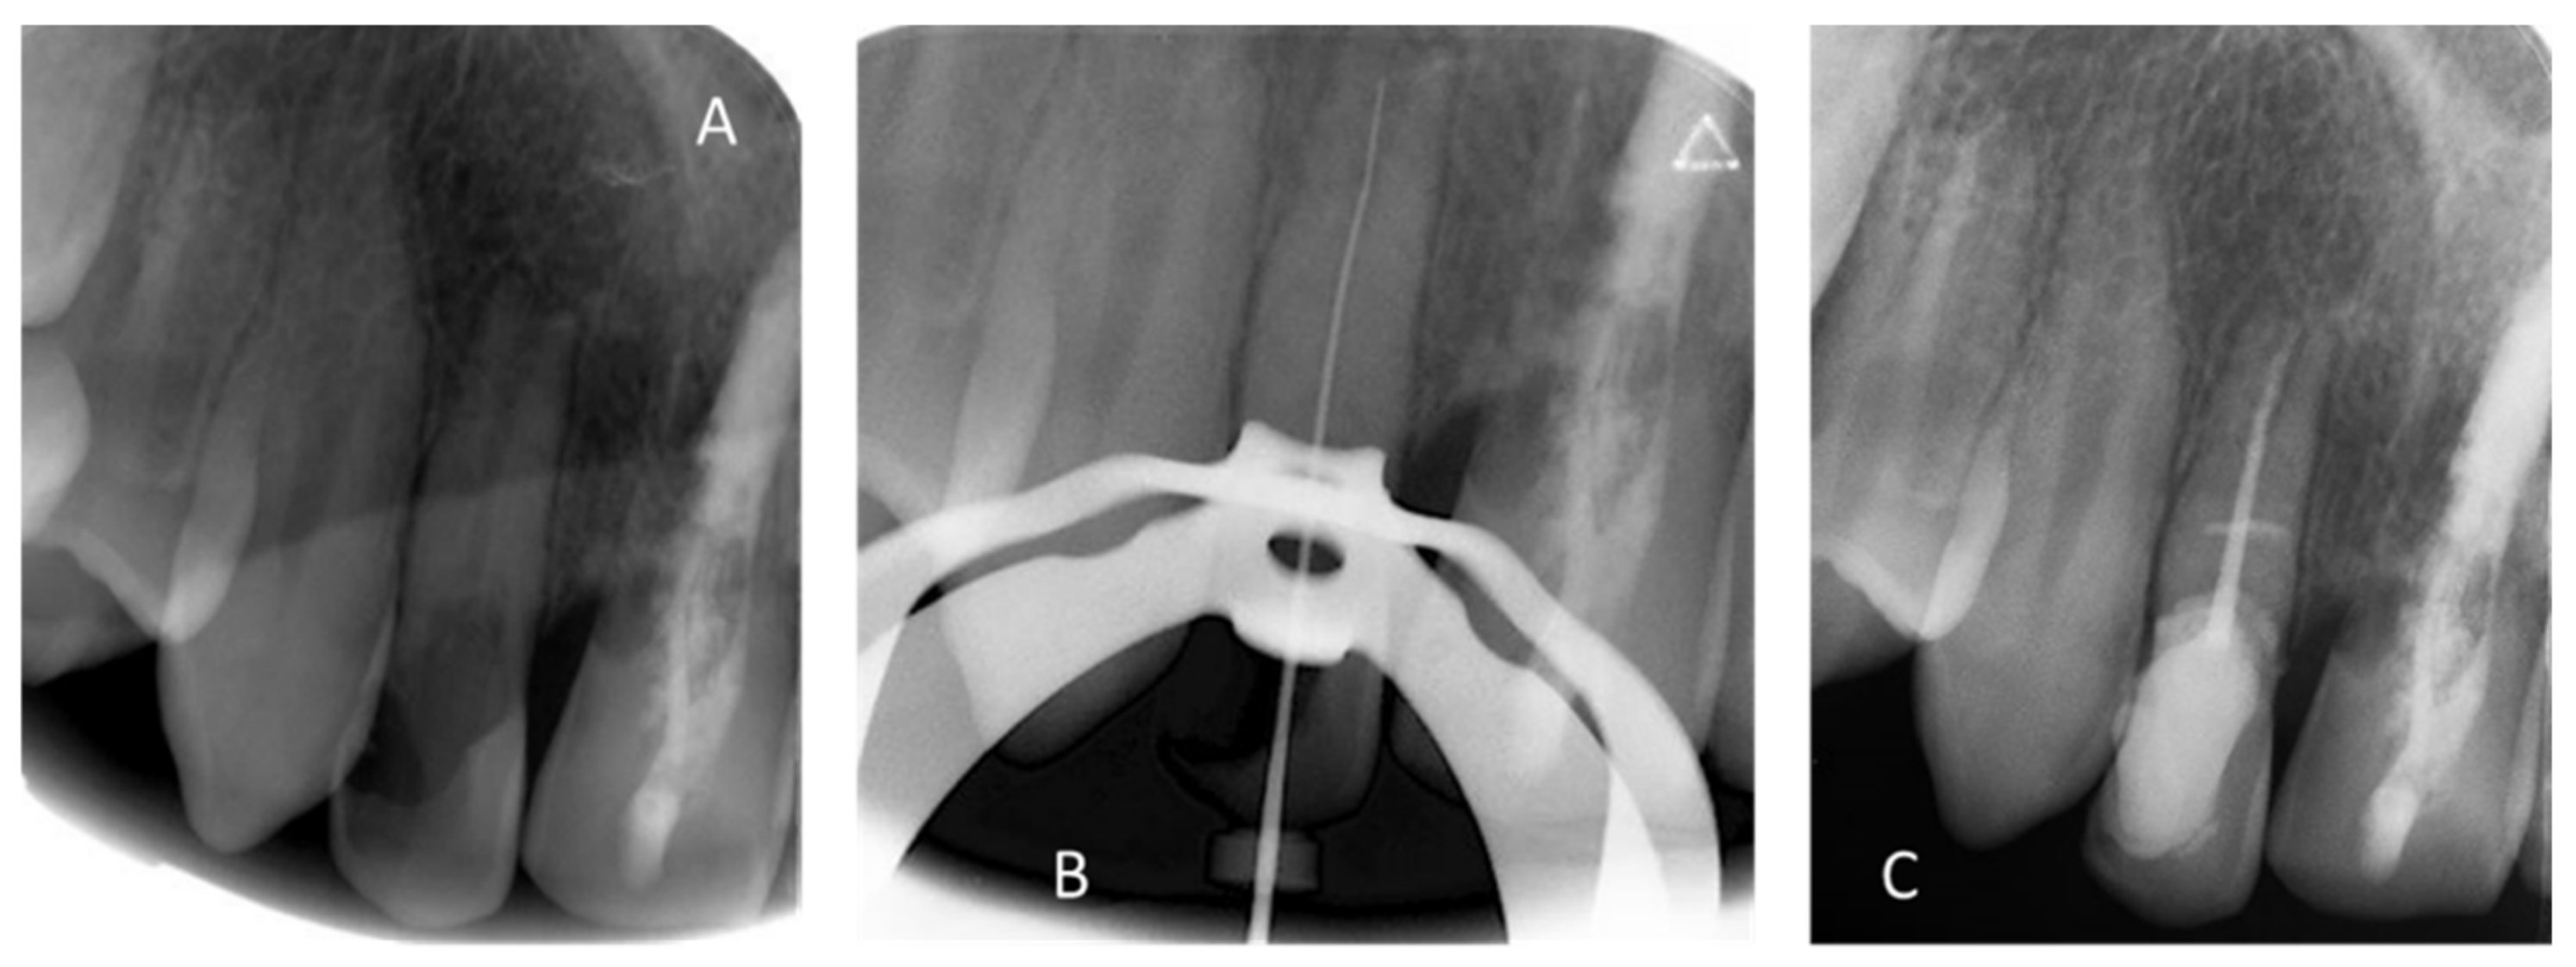

| April 2018 | “pink spot” lesions/invasive cervical resorption of class III according to Heithersay classification [15,16]/negative response to vitality test | Slight mobility/complete root inflammatory resorption around the gutta percha filling | “pink spot” lesions/invasive cervical resorption of class II according to Heithersay classification [15,16]/negative response to vitality test | |

| Figure 3, Figure 4 and Figure 5 | ||||

| May 2018 | Buccal and palatal flap of upper right anterior teeth without discharge/curettage of the granulation tissue/endodontic (lesion was of interest to the pulp)/restoration with a composite resin under dam/endodontics treatment with sodium hypochlorite irrigation and obturation at BioRoot™ and calibrated cone | Buccal flap without discharge from upper left anterior teeth/curettage of the granulation tissue/restoration with a composite resin under dam | ||

| Preservation of the bone capital until the implant solution | ||||

| Figure 6 and Figure 7 | ||||